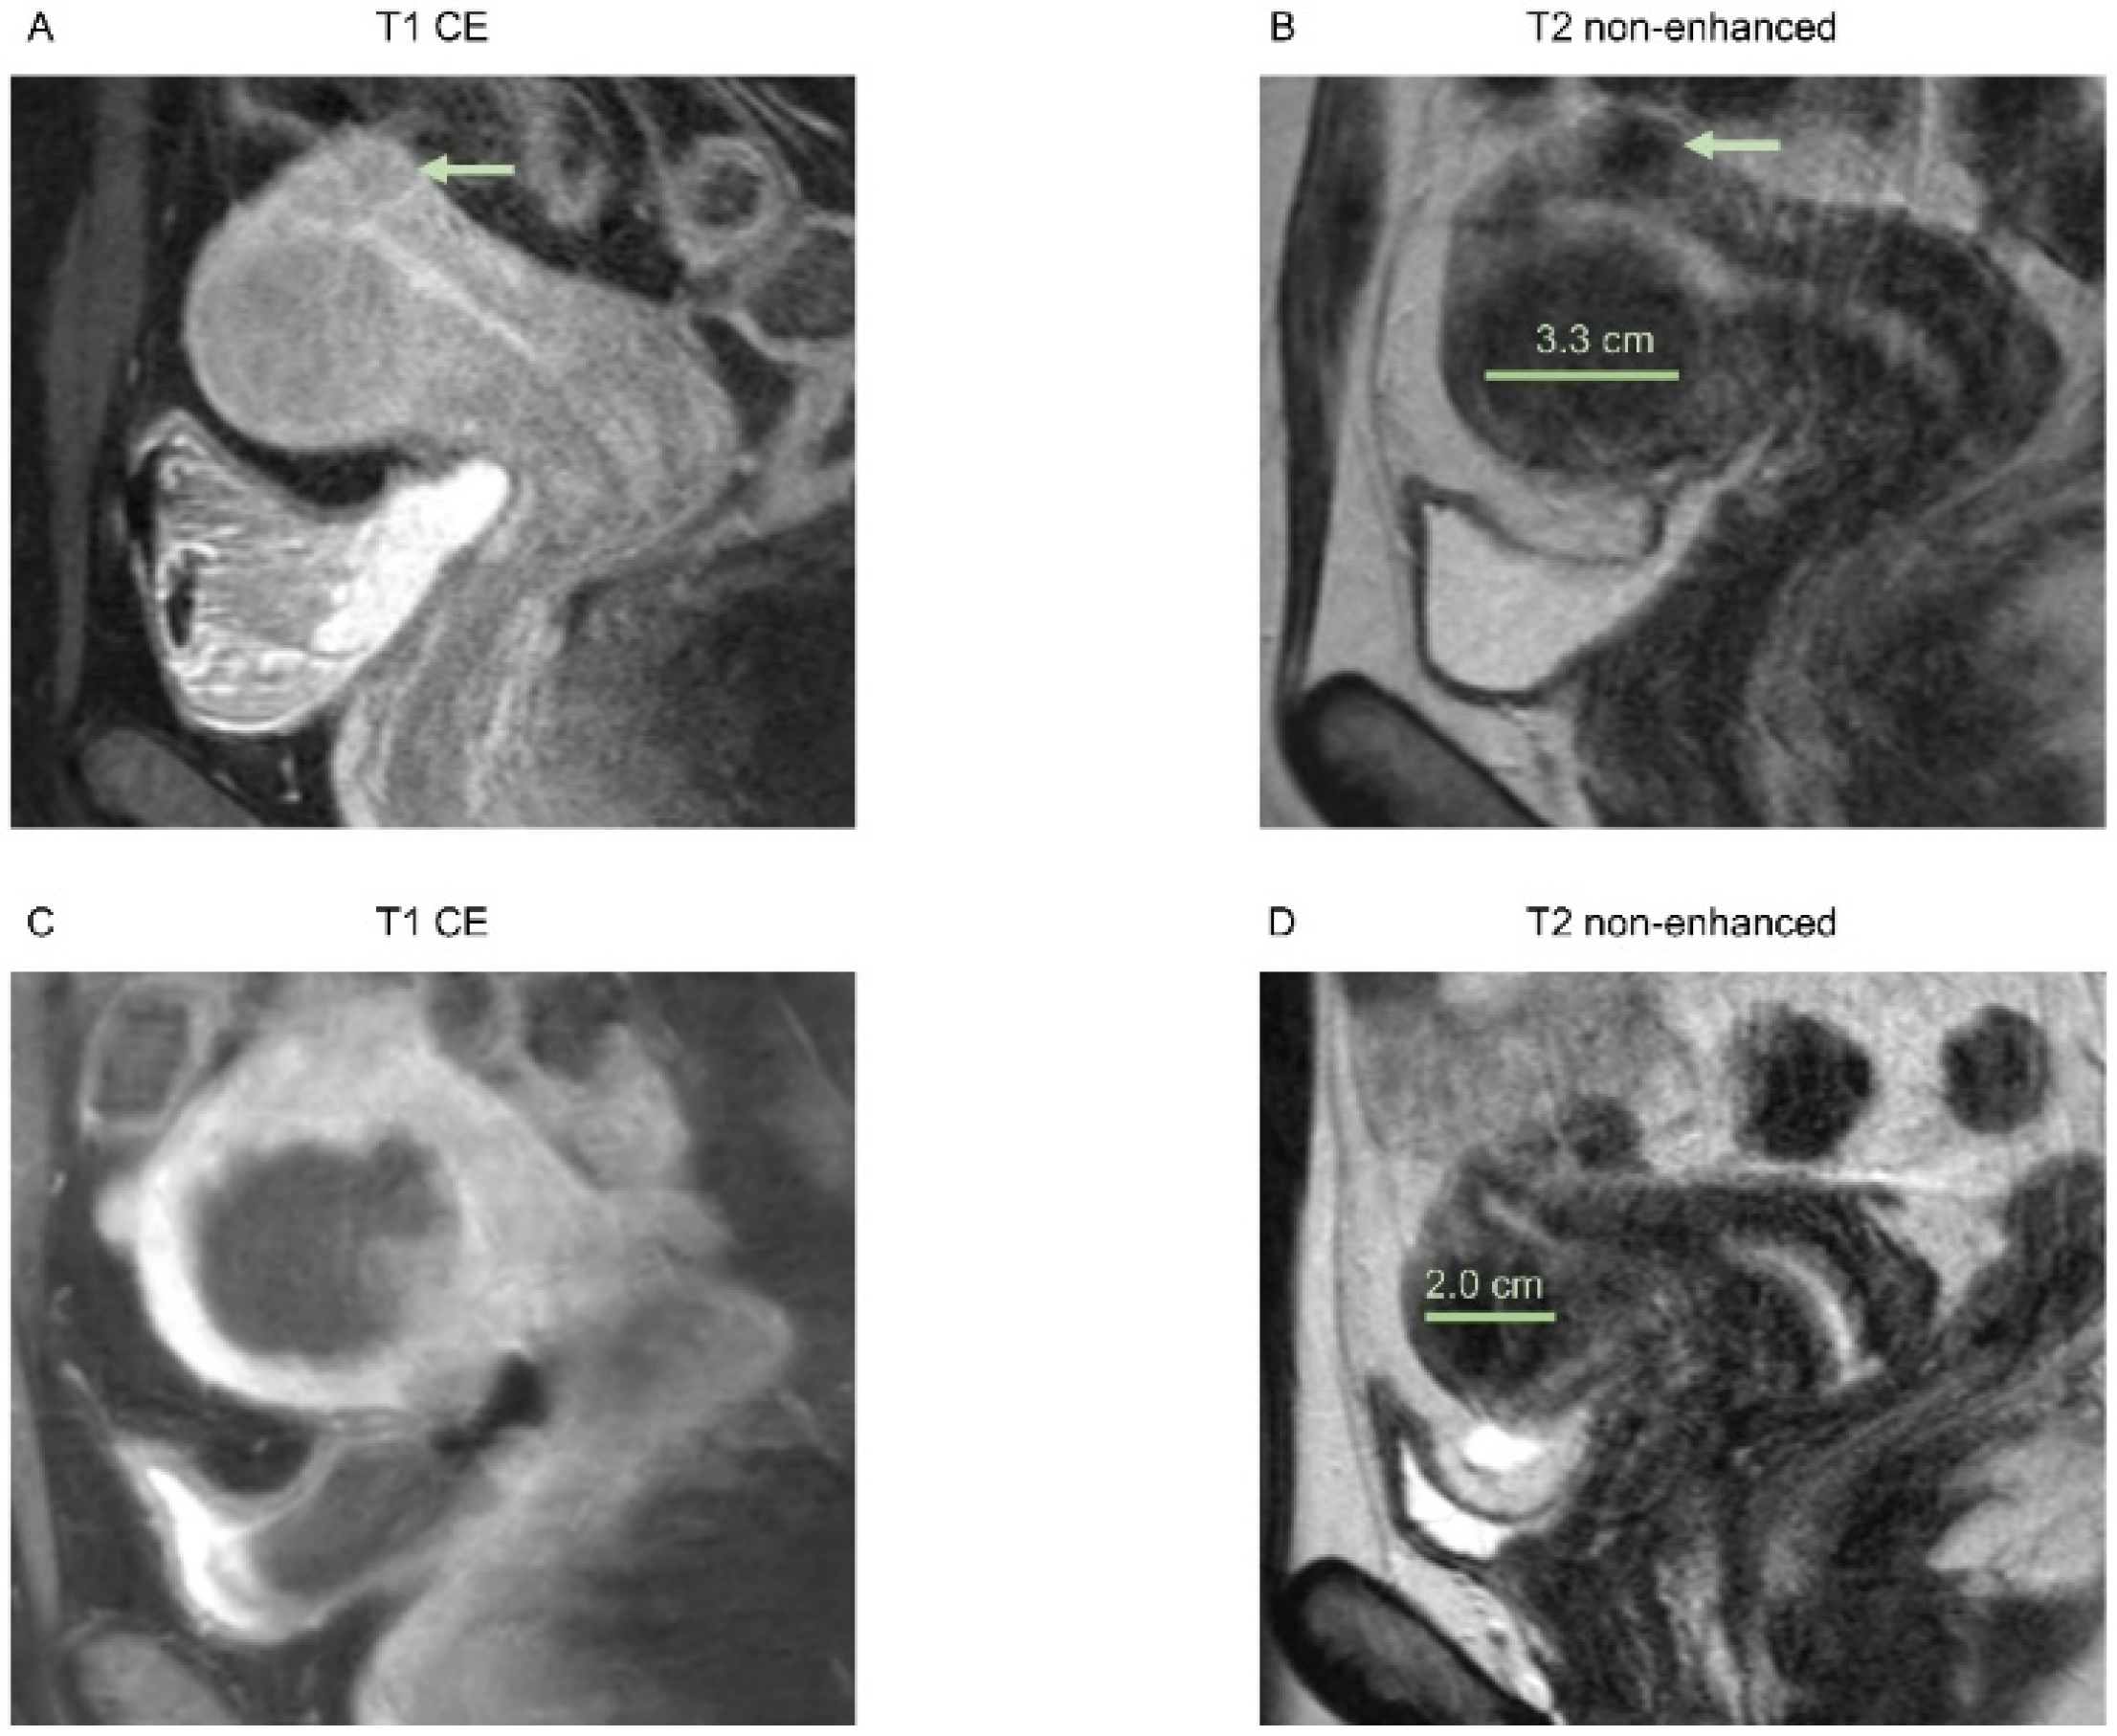

In Figure 1 and Figure 2, examples of an MRI of both groups are shown.

Figure 1. Images of a 51-year-old patient with solitary intramural uterine fibroid in the posterior wall, Funaki grade 2. (A) Contrast-enhanced T1-weighted and (B) T2-weighted images 2 weeks before HIFU treatment, sagittal reformation. Pre-interventional maximum diameter was 7.5 cm. (C) Immediate post-interventional T1 contrast-enhanced image with a volumetric assessed NPV of 61%, sagittal reformation. (D) T2-weighted image 6 months after intervention with a maximum diameter of 4.1 cm, sagittal reformation.